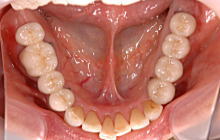

インプラント治療例 2

術前の状態

福岡 インプラント 福岡 インプラント

インプラント治療後の状態

左上に4本、右下に2本のインプラントを埋入したケースです。